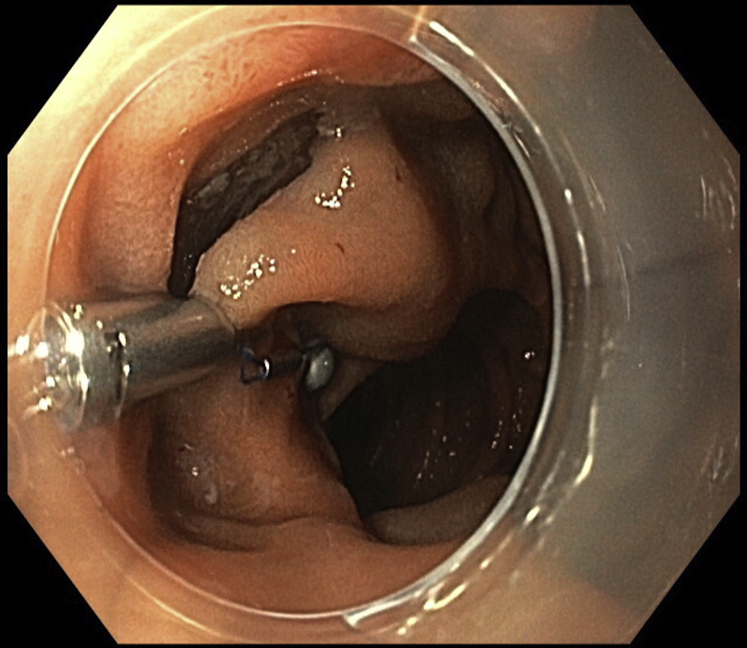

Figure 2.

Deployment of the system in the proximal mucosal flap.